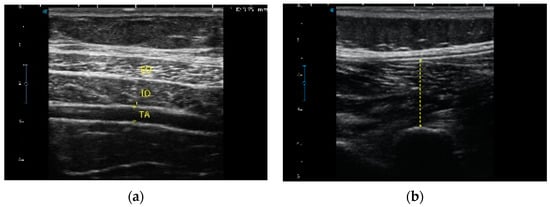

2.3. Sonographic Assessment of the LM and TA

2.4. Image Analysis